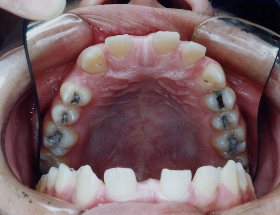

主訴:歯のガタガタ(特に下の前歯)を治したい。できれば歯を抜きたくない。診断名:上下前歯部叢生。43歳。前歯は透明,奥歯は金属製のエッジワイズ装置にて治療。歯は抜いていませんが、特に下の歯はできるだけ多くの歯を削って細くしています。治療期間1年2か月。治療費:矯正料670000円 調整料 2000円~5000円が約14回。歯を抜かずに歯並びのガタガタをとる症例としてはガタガタの量が最も大きい症例だと思います。この患者さんは横顔がきれいで、口元が出ていなかったので、この方法をとることができました。奥歯の後ろの余裕を作るために、下の親知らずだけは抜いています。もともとガタガタが大きいので、後戻りの可能性も高くなるので、前歯の裏をワイヤーで留めています。取り外し式のリテーナーもしっかりとはめていただいています。ストリッピング(歯を削ること)をしすぎると知覚過敏が出ることがあるので、できるだけ多くの歯に分散して少しづつ慎重に削りました。